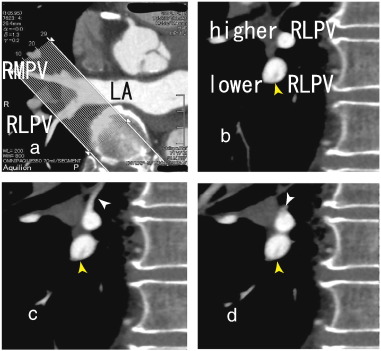

The patient was a 70-year-old man with angina pectoris, and he presented with recent chest pain. He had been treated with percutaneous coronary intervention and had four stents in the coronary arteries. A 64-MDCT scan was performed to evaluate recent chest pain. The scan did not show a coronary artery stenosis and no restenosis in the stents. However, a thrombus in the right lower pulmonary vein (RLPV) was shown in sagittal images (Figs. 1b to 2d) as a defect in contrast enhancements. Axial images of that portion are shown in Fig. 1a. A 64-MDCT scan is useful for identifying pulmonary vein thrombi and preventing stroke because 64-MDCT can depict pulmonary vein thrombi in detail, which helps to estimate the effects of anticoagulants.

Fig. 1.

b, 64-MDCT images showed a thrombus in the lower right lower pulmonary vein (lower RLPV) (yellow arrowhead), which seemed to attach to the inferior wall of the lower RLPV. In Fig. 1c, a small vessel approached to the superior wall of the higher RLPV (white arrowhead) and then in Fig. 1d, there appeared a thrombus located on the superior wall as a defect in contrast enhancements (white arrowhead) and extended toward the left atrium (LA) (Fig. 2a to c) that was attached to the superior wall of the lower RLPV (white arrowhead). In Fig. 1d, the higher and lower RLPVs merged into the RLPV.

The thrombus attached to the inferior wall of the lower RLPV extended toward the LA.

Fig. 2.

a and Fig. 2b, a small dark inferior vessel (double yellow arrowhead) has a thrombus that seems to joint a pre-existent thrombus extending from the lower RLPV (Fig. 1b) to the LA (Fig. 2c, yellow arrowhead) and attached to the inferior wall of the RLPV. The upper and lower RLPVs merged into the RLPV (Fig. 2c). In Fig. 2d, the RLPV and the right middle pulmonary vein (RMPV) merged and flowed into the LA. LA; left atrium, RLPV; right lower pulmonary vein, RMPV; right middle pulmonary vein.